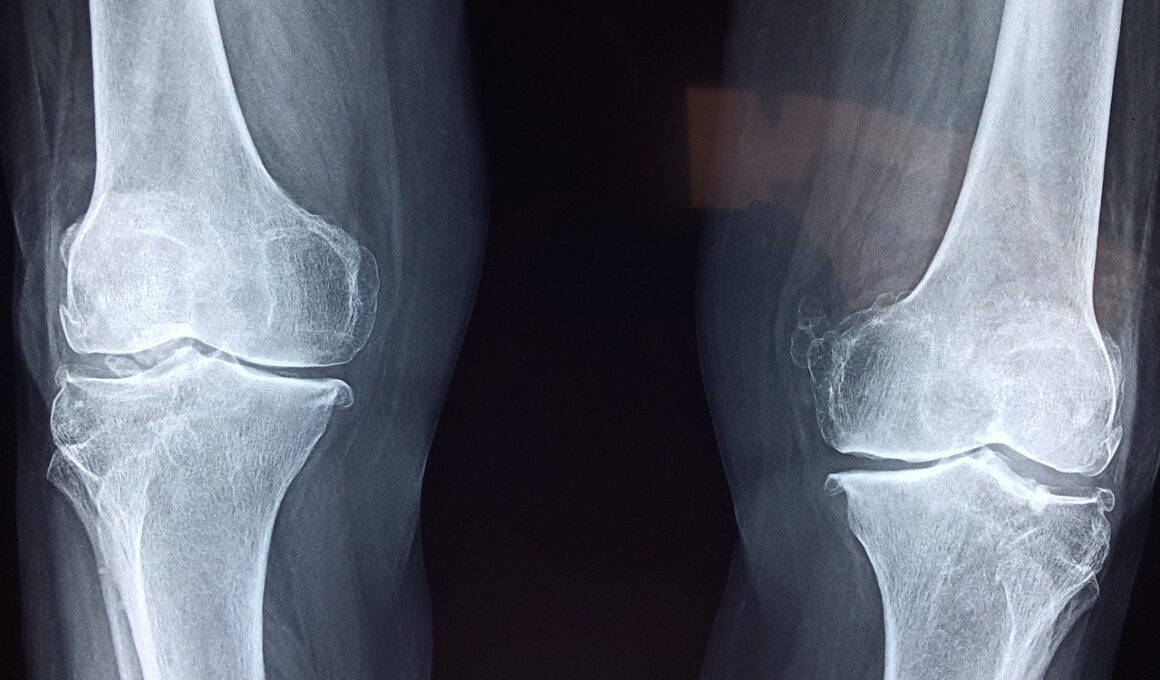

The journey to longevity has frequently become intertwined with various health practices and strategies. Among these, ensuring optimal bone health emerges as a critical focus. Strong bones not only support structural integrity but also play a crucial role in overall health and longevity. By understanding the biological mechanisms behind bone formation and resorption, individuals can employ targeted strategies that bolster bone density and strength. Some effective methods include weight-bearing exercises, adequate nutritional intake, and lifestyle modifications. Taking charge of bone health is an empowering step on the path to longevity.

Regular assessments of bone health should be part of a proactive approach to longevity. Doctor visits that include bone density tests can provide essential insights into individual bone health status. Early detection of issues such as osteoporosis can enable timely interventions, preventing further complications. Moreover, continuous education about bone health through reliable sources keeps individuals informed about new research findings, therapies, and lifestyle changes. Keeping track of advancements in bone health can influence personal choices positively, leading to the adoption of innovative strategies that bolster longevity and improve quality of life significantly.